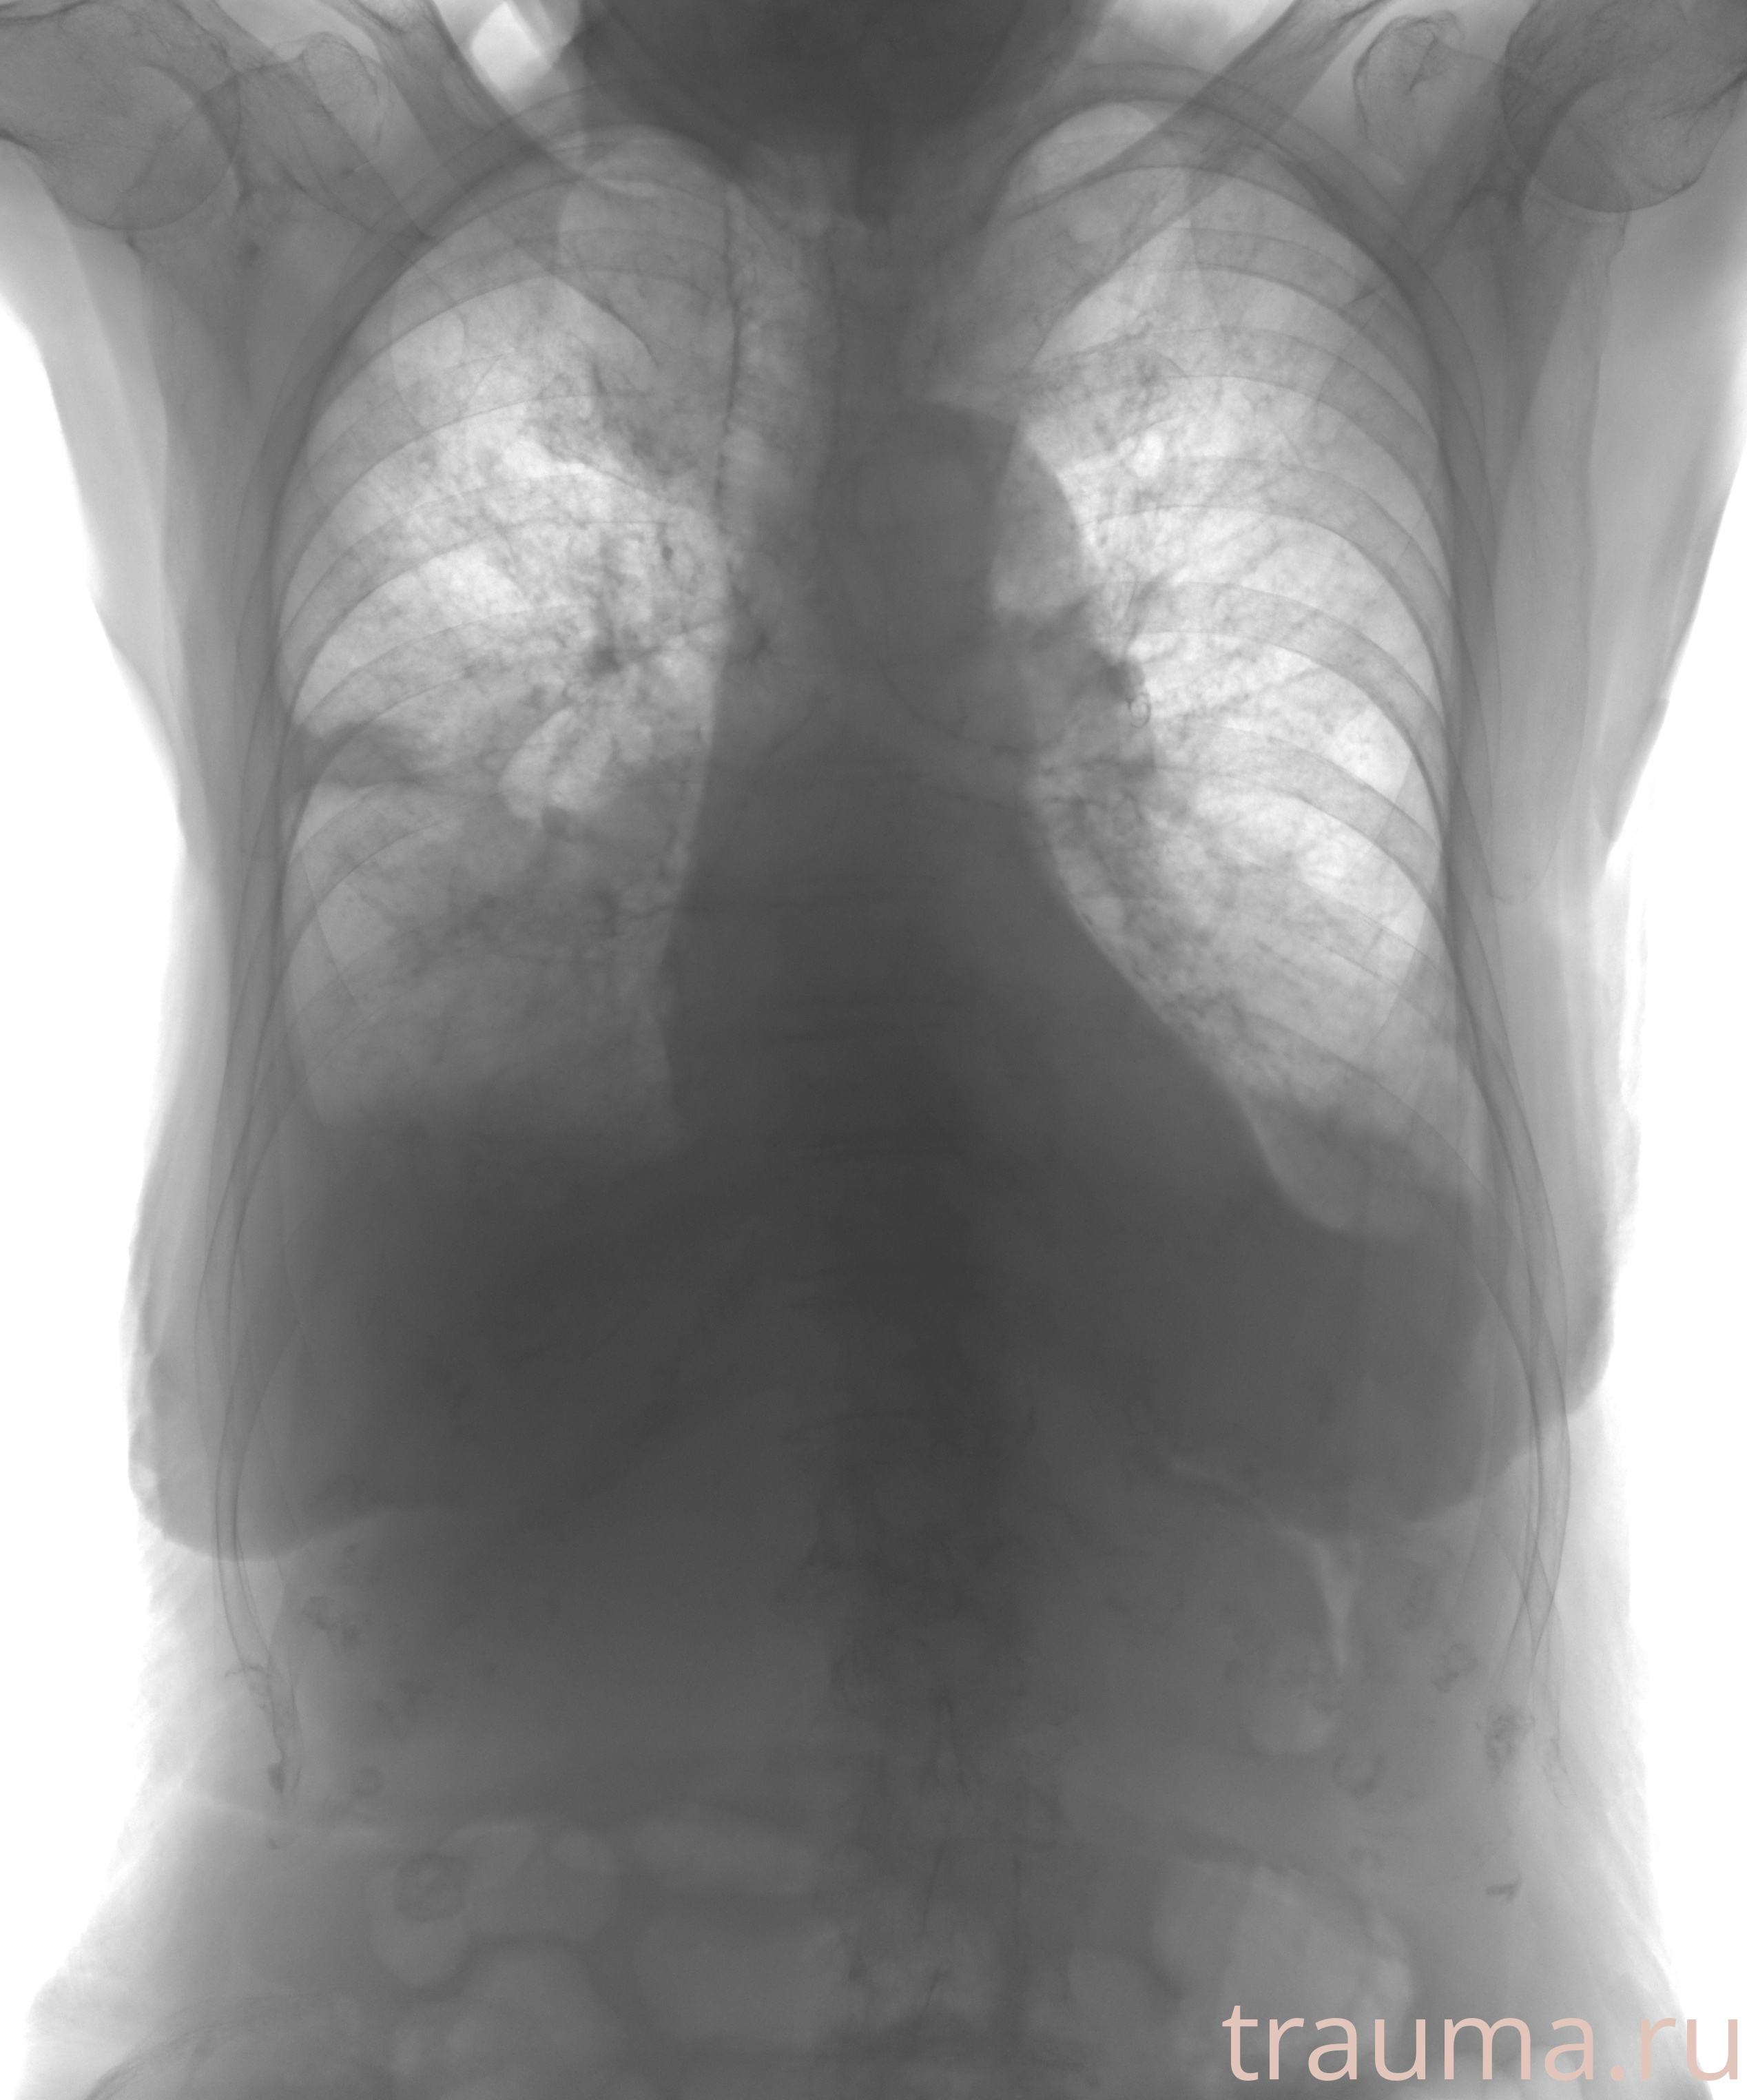

Рентгенограммы

Рентген на дому: по вашему адресу приезжает врач-рентгенолог, травматолог-ортопед с мобильным рентгеновским аппаратом, проводит диагностику травмы или заболевания, делает необходимые рентгенограммы, дает рекомендации по дальнейшему лечению. Получить качественные снимки в домашних условиях возможно благодаря уникальной методике, разработанной МосРентген Центром для института  Склифосовского

при переломе шейки бедра и пневмонии от компании МосРентген Центр - партнера Института имени Склифосовского